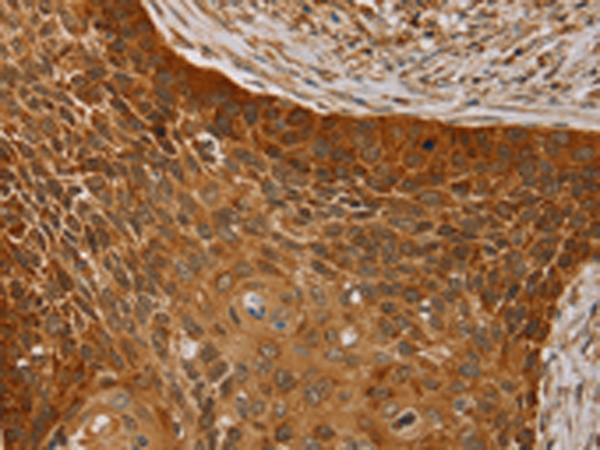

分类: 科研抗体货号: P01604别名: CN1; CNI; CN-I; CN1A; CN-IA应用: IHC反应种属: Human, Mouse